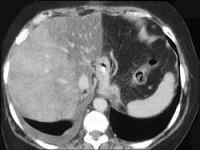

问题 男,66岁,肥胖,有糖尿病史,CT检查如图,最可能的诊断是 ( )

选项 A.局灶性脂肪肝 B.肝硬化肝癌 C.肝血管瘤 D.肝胆管细胞癌 E.肝淋巴管瘤

答案 A